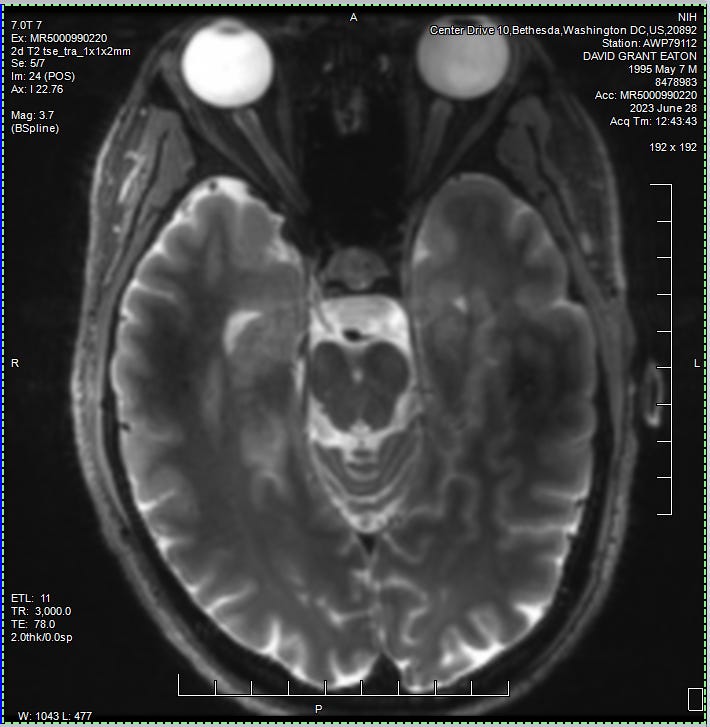

Anyways, Ann comes to introduce herself and brings with her a stack of consent forms. She did a great job of explaining some of the finer details of the studies. Along with their confidentiality practices, compensation, and all of that good stuff. I took a bit of time to read through the paperwork. I knew I was going to sign it anyway. But it's always good to at least glance over the fine print before signing your name away. She also went into the details of what I was going to be experiencing for the remainder of the day. In addition to testing my blood for genealogy, they were also going to get a full baseline of my physical and mental well being. This included a full STI/STD panel, EKG, chest X-ray, COVID test, and physical.

We then headed off of the unit to attend my first rounds of testing. Everywhere I went from this point on required a scan of my wristband, as well as a recitation of my name and date of birth. I did my first ever EKG and Chest X-ray. Zzzzap. I’d never seen such machinery in person before. It was pretty darn cool to see it all in action, and in each of these rooms the operators were super kind and clearly well experienced in their respected fields. I was also surprised that there wasn’t much waiting for these tests. I’m assuming that this study had some kind of priority to move things along rather quickly.

Ann came back to check on me at some point. She was delighted to share that my COVID test came back negative, which meant I was now free to go about the common areas of the unit. She also mentioned that I was welcome to attend my first evening group, which started at 6:45pm. Our last order of business was to go through a simple MRI screening. She went down a long list of questions, relating to any kind of metal that may have found its way into my body. Pacemakers, titanium plates, that kind of stuff. Most of these things I had never even heard of. So we quickly made our way through the list, until towards the bottom she asks: “ever been shot with a BB gun?”